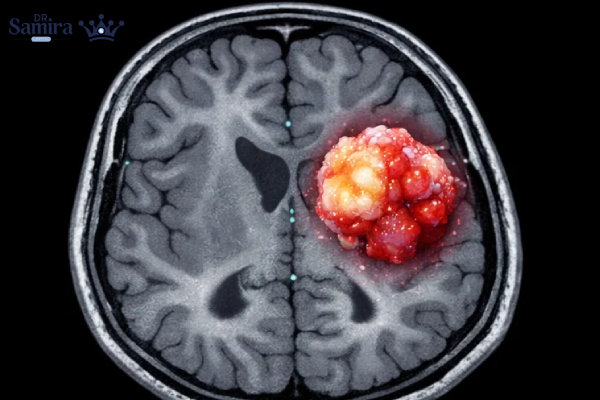

تشخیص این تومورها اصولا با استفاده از MRI مغز انجام میشود. در تصویربرداری، گانگلیوگلیوما اغلب بهصورت ضایعهای با حدود نسبتا مشخص و ترکیبی از بخشهای کیستیک و جامد دیده میشود. در تصاویر T2 و FLAIR افزایش سیگنال مشاهده میشود و میزان جذب ماده حاجب متغیر است. در CT scan، وجود کلسیفیکاسیون نسبتاً شایع است. تشخیص قطعی تنها با بررسی پاتولوژیک و ایمونوهیستوشیمی امکانپذیر است.

بررسی پاتولوژی و آزمایشهای تکمیلی

در بررسی میکروسکوپی گانگلیوگلیوما، نورونهای دیسمورفیک بزرگ در کنار سلولهای گلیال نئوپلاستیک دیده میشوند. مارکرهایی مانند GFAP، NeuN و Synaptophysin در تشخیص کمک کننده هستند. در گانگلیوسیتوما، تنها نورونهای بالغ غیرطبیعی مشاهده میشود و شاخص تکثیر سلولی (Ki-67) بسیار پایین است.